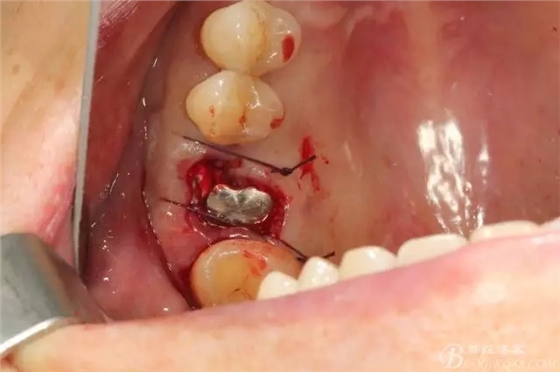

備洞只是稍微修整就可以,因?yàn)閷?shí)在太大了也沒啥好讓我們折騰的骨頭了

備洞的時(shí)候當(dāng)然想盡一切辦法讓顎側(cè)骨頭往頰側(cè)推,使得種植體的頰側(cè)有人為做出來的骨壁

植入以后,方向當(dāng)然還是我的強(qiáng)項(xiàng)吧 不過這個(gè)種植體稍微靠了點(diǎn)遠(yuǎn)中了

種植體頰側(cè)還是沒有完全被骨壁包繞,但是不要緊,不需要植骨

穩(wěn)定性還可以,就直接上了愈合基臺(tái)

頰側(cè)空隙塞了膠原塞 簡(jiǎn)單縫合,全程0翻瓣,很高調(diào)的告訴患者,術(shù)后不太會(huì)有反應(yīng)的。